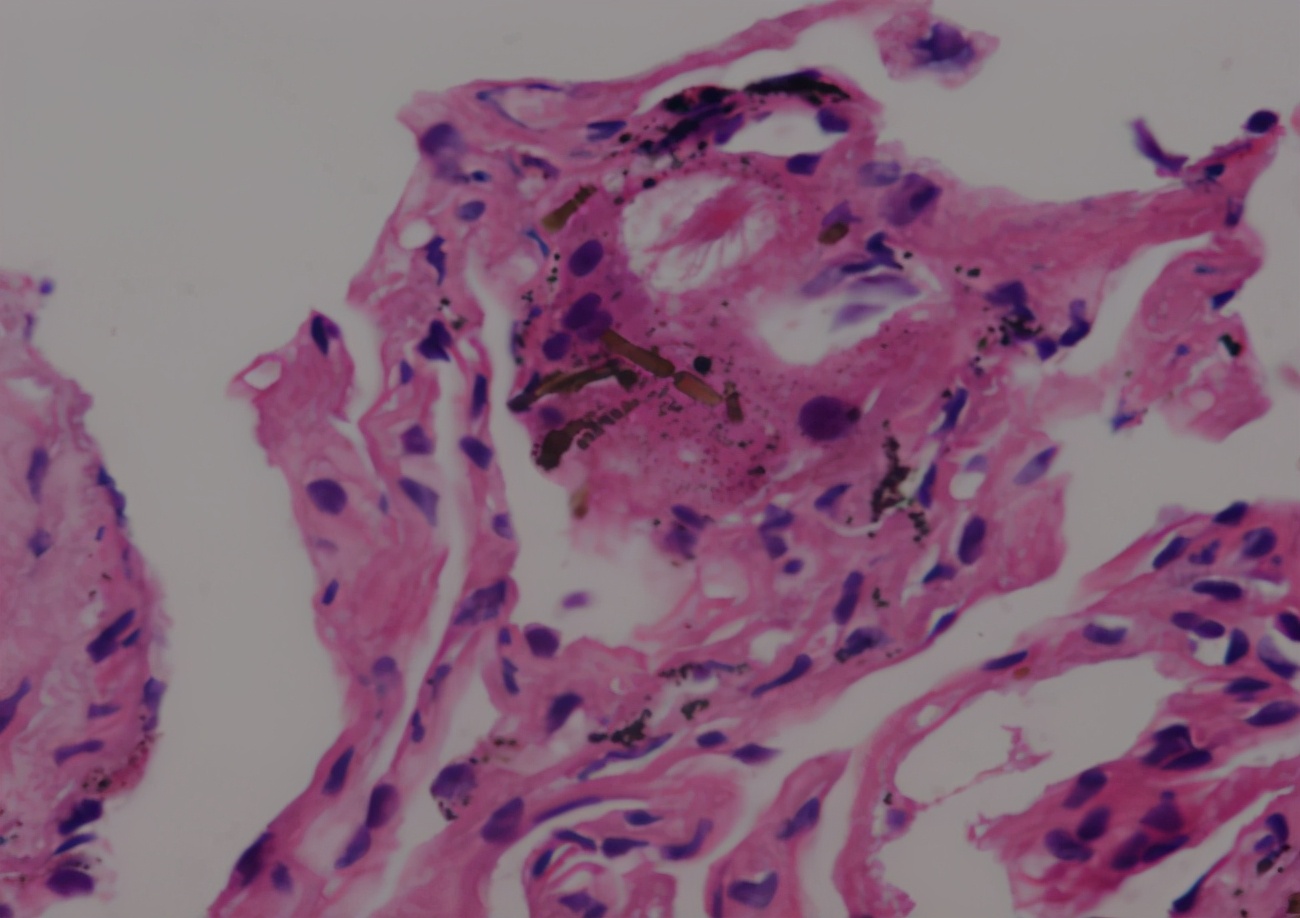

就在这时,肺穿刺检查特染结果回报:(右肺)少量肉芽肿性炎,特染未见特异性病原体,见少量石绵小体,请结合临床及相关职业史(图12)。

图12:肺穿刺检查特染结果

石绵肺的诊断主要依据详细的职业接触史,再结合特征性的影像学改变、限制性通气功能障碍等做出,对于不典型病例,可通过肺活检等介入手段获取病理学依据。石绵小体(石绵纤维被含铁蛋白包裹后形成)是具有诊断意义的特征。该患者并无相关职业暴露史,加之影像学缺乏特异性胸膜肥厚伴钙化斑、肺间质纤维化等表现,虽然有限制性通气功能障碍、弥散功能减退,但仍然很难在一开始就联系到石绵肺这个疾病。我们再次仔细询问患者的生活史、职业史,患者认真回忆后提到:从事船员工作期间,曾长期参与搬卸工作,其中就包括石绵材料。